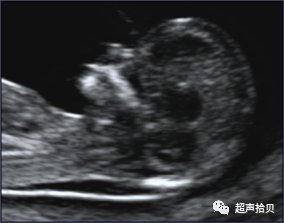

2)21- 三体综合征动物模型

16三体小鼠人类21三体的动物模型——16三体小鼠,有心脏畸形和淋巴管异常。

在 14-16天,出现颈后皮下液体聚集。